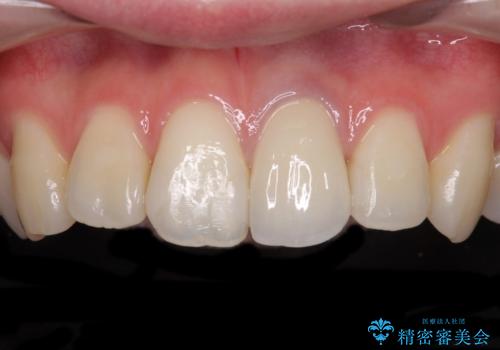

オーダーメイドタイプのクラウンを選択いただいたので、まるで天然の歯と見間違うほど自然に仕上がり、患者様には大変満足していただきました。